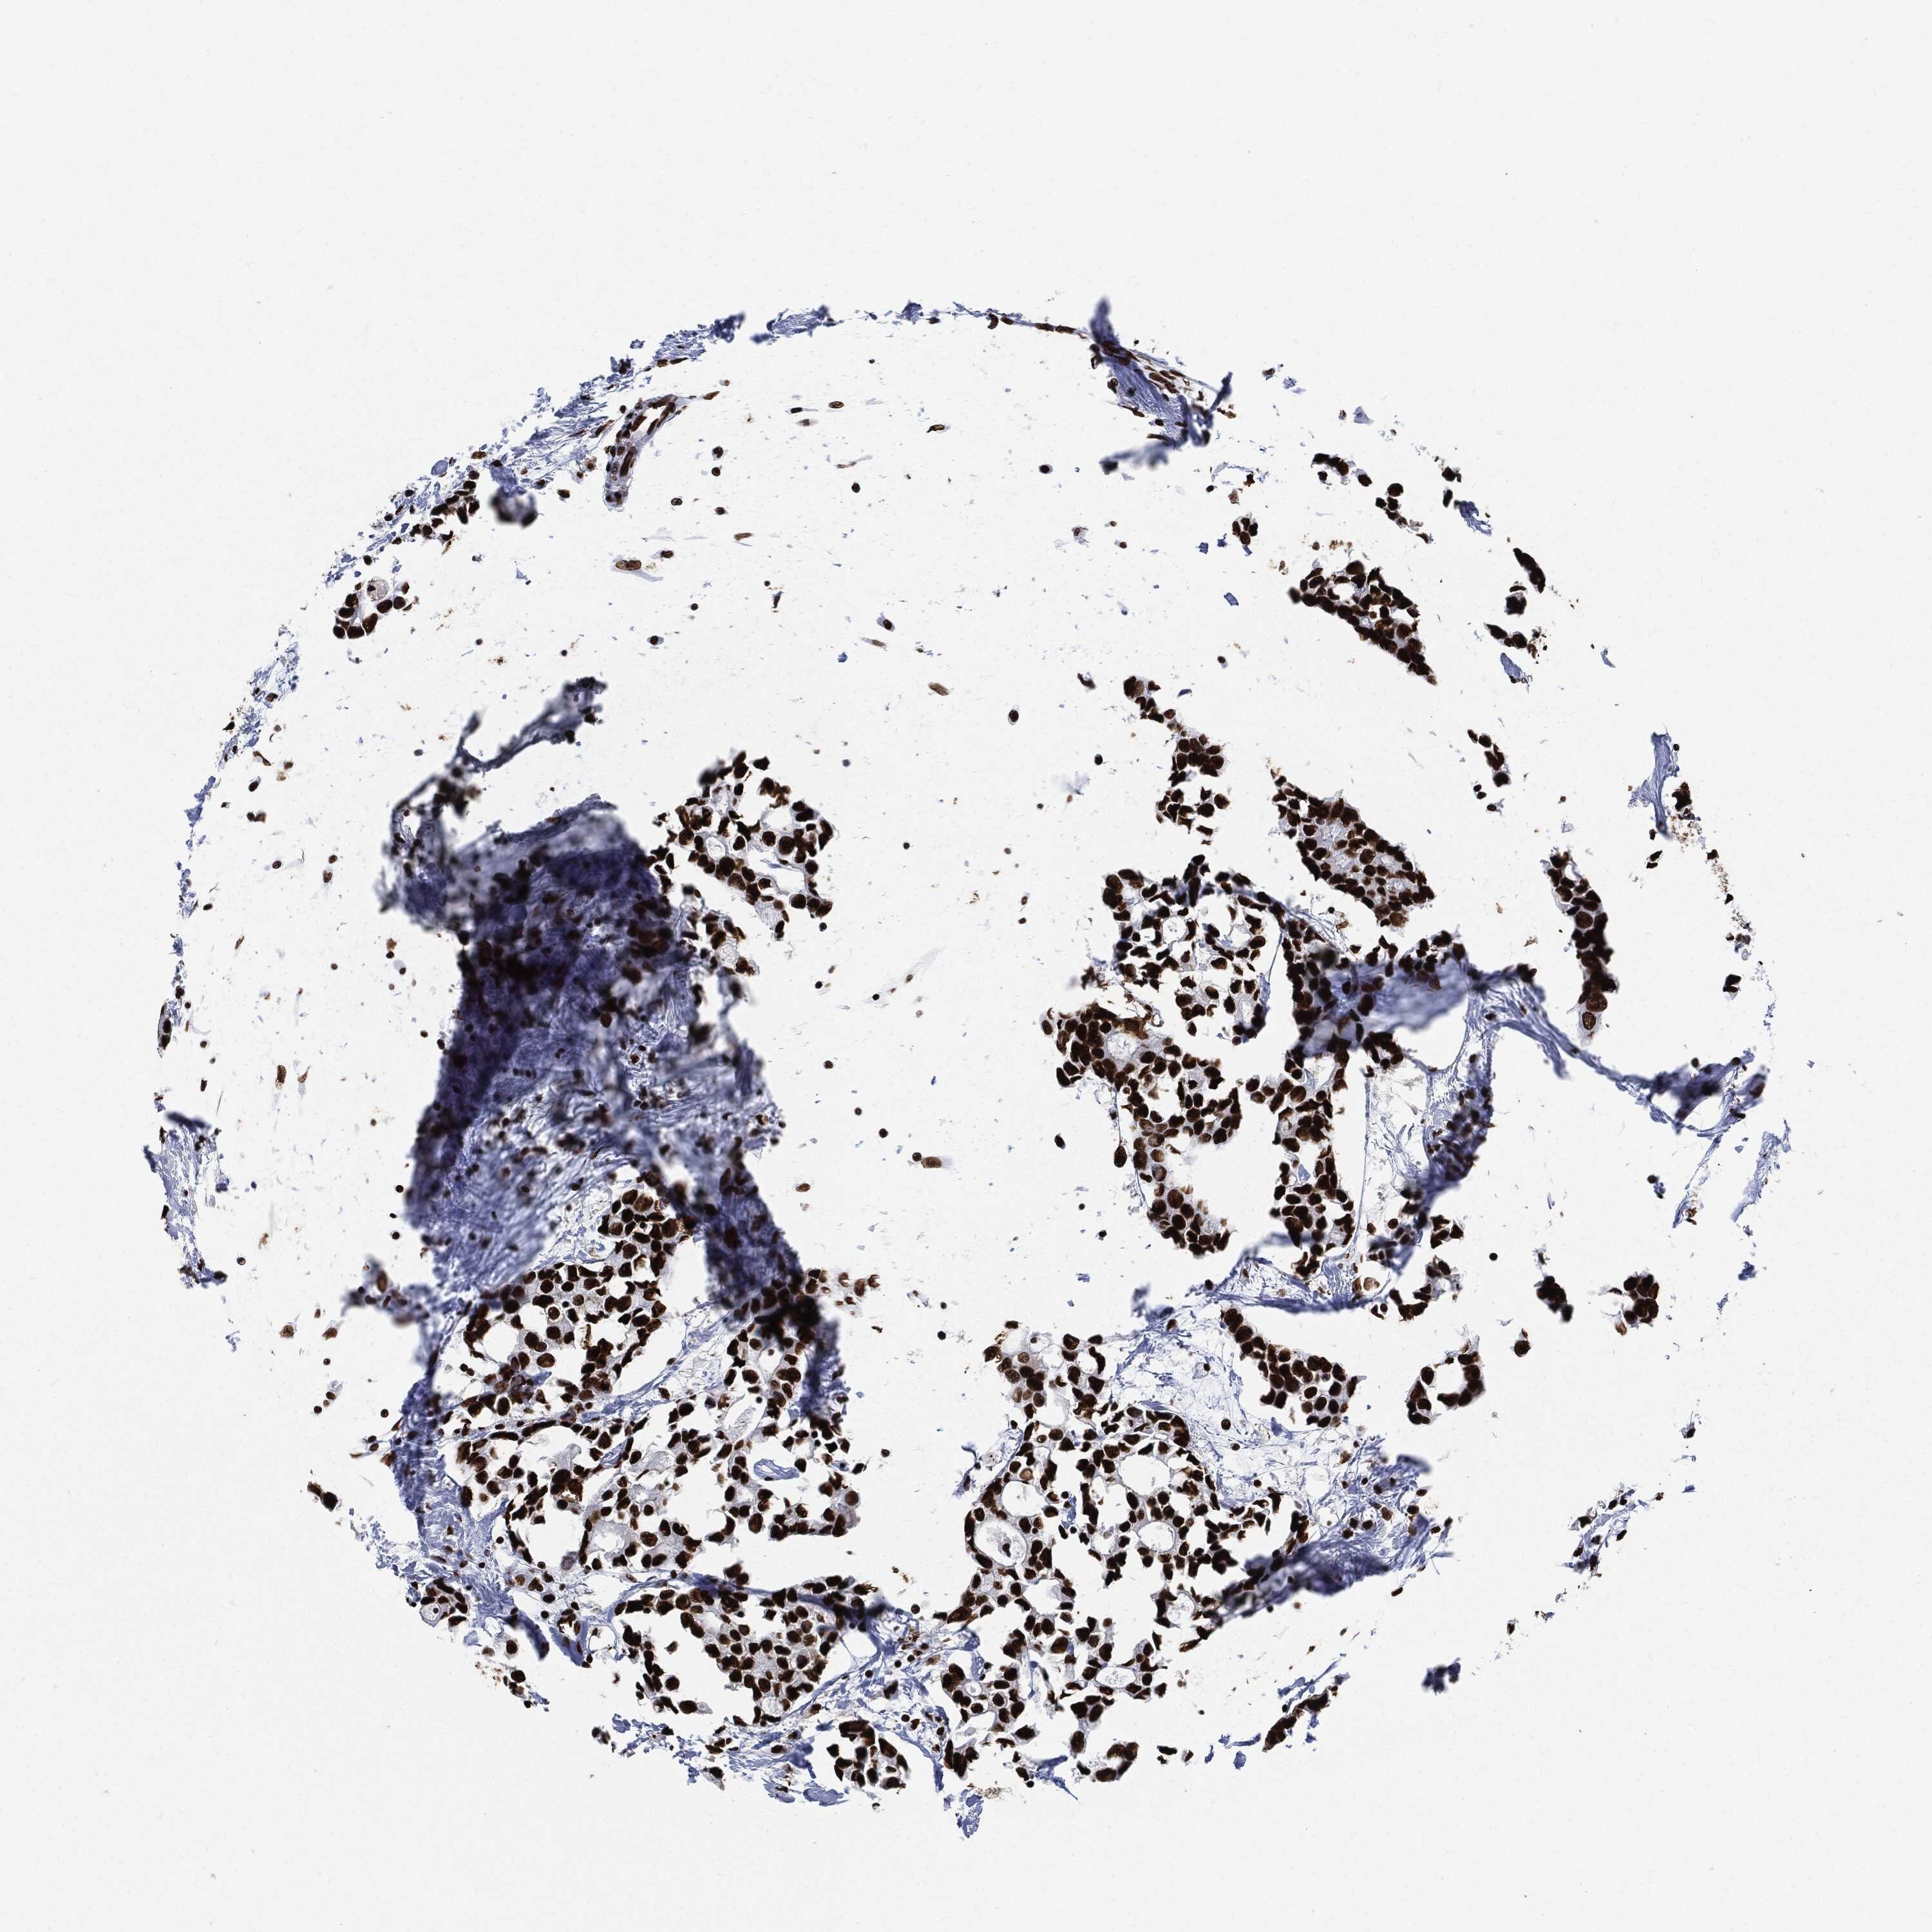

BRCA TCGA BRCA VALIDATION PROTEIN EXPRESSION